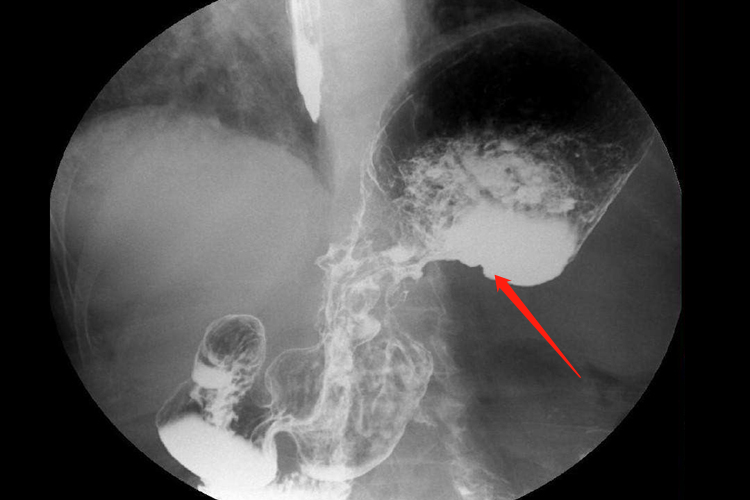

X线征象主要有龛影、充盈缺损、胃壁僵硬胃腔狭窄、黏膜皱襞的改变等。